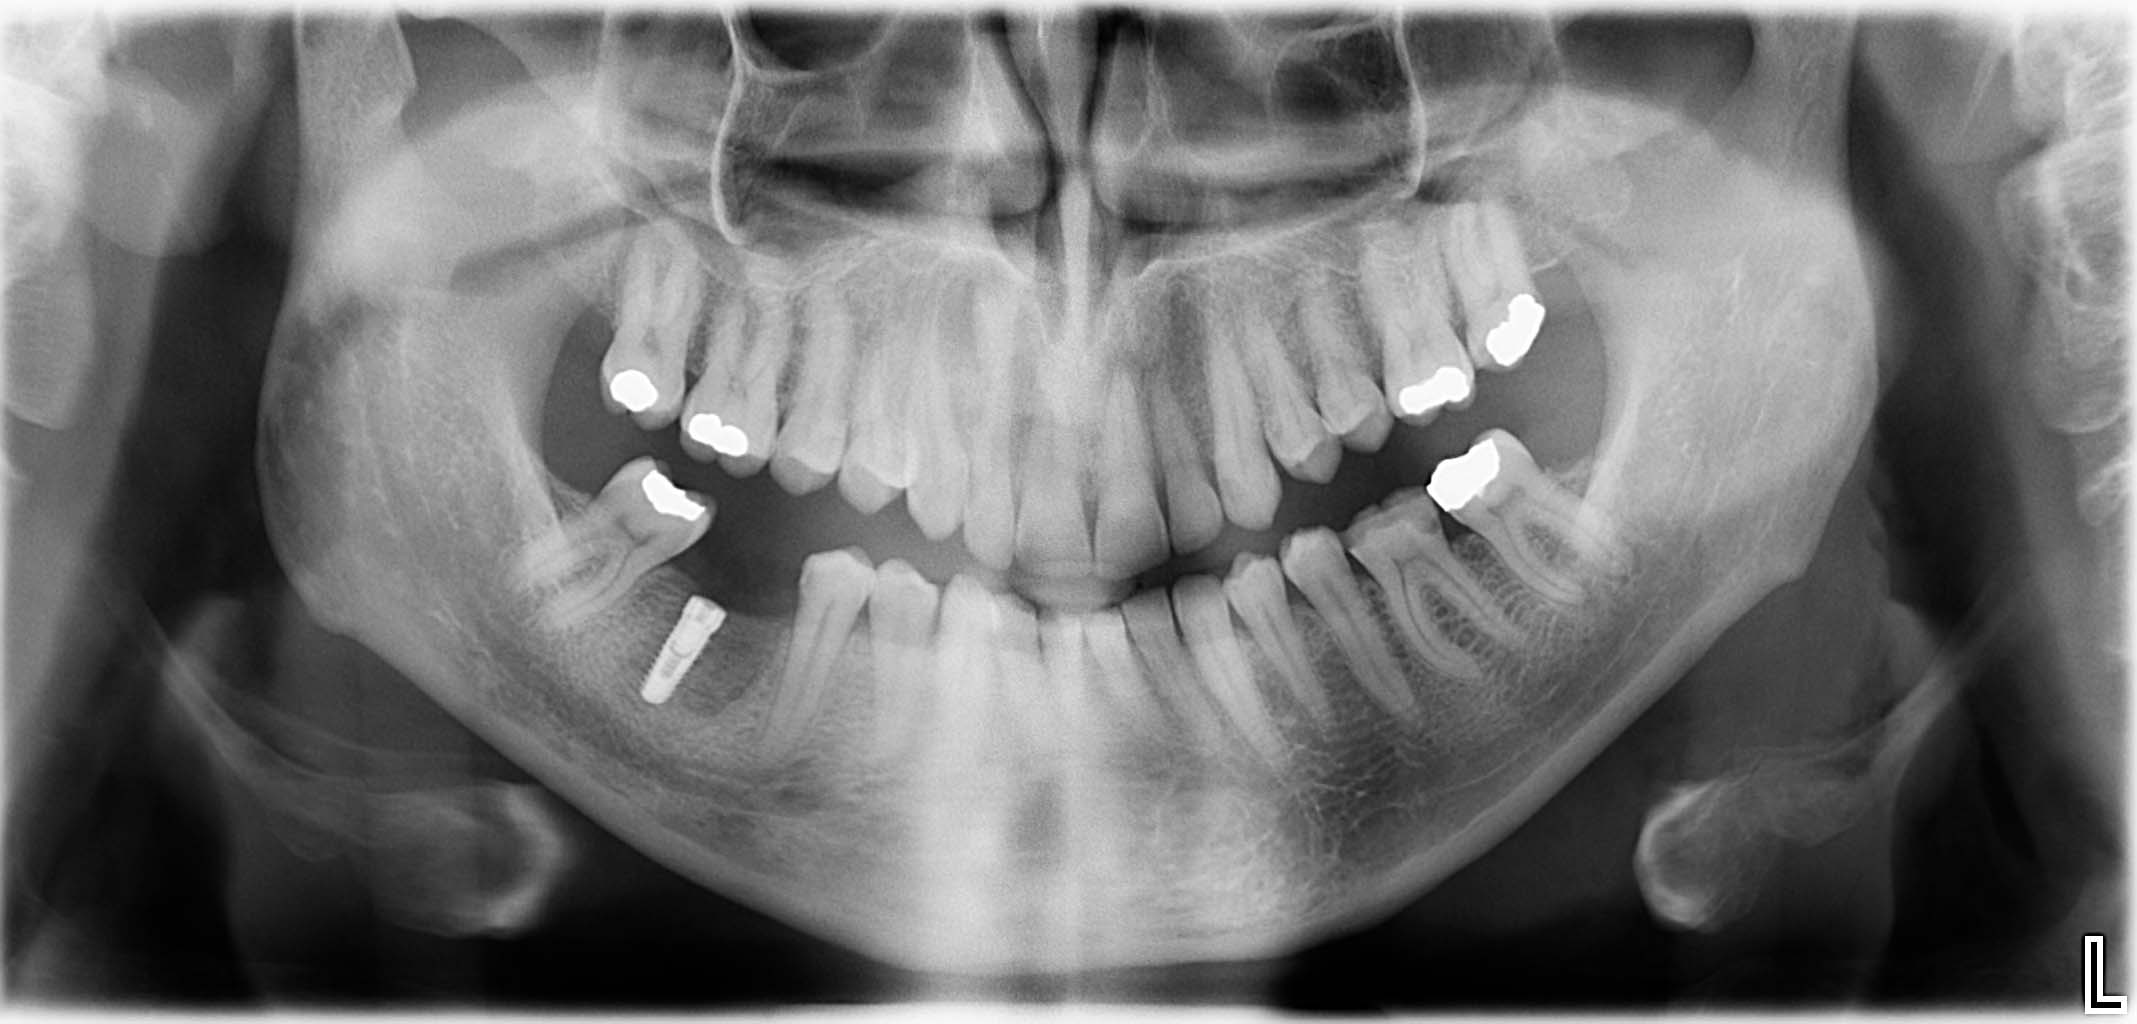

Erfolgreich implantierte Patientenfälle (klinische Fotos)